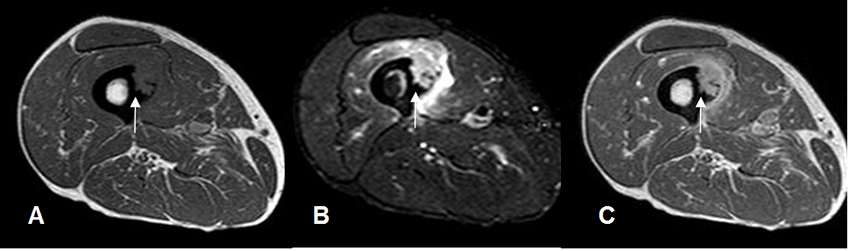

Fig 50 B. Compromiso menor de la cortical .

A: RM axial en T1, B: RM axial en STIR y C: RM axial en T1 con contraste. Sarcoma de tejidos blandos, que compromete un 20% de la circunferencia de la cortical.